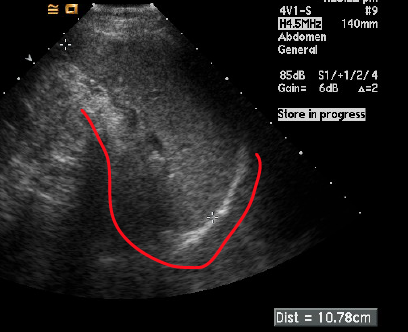

what plane was this image taken in?

transverse